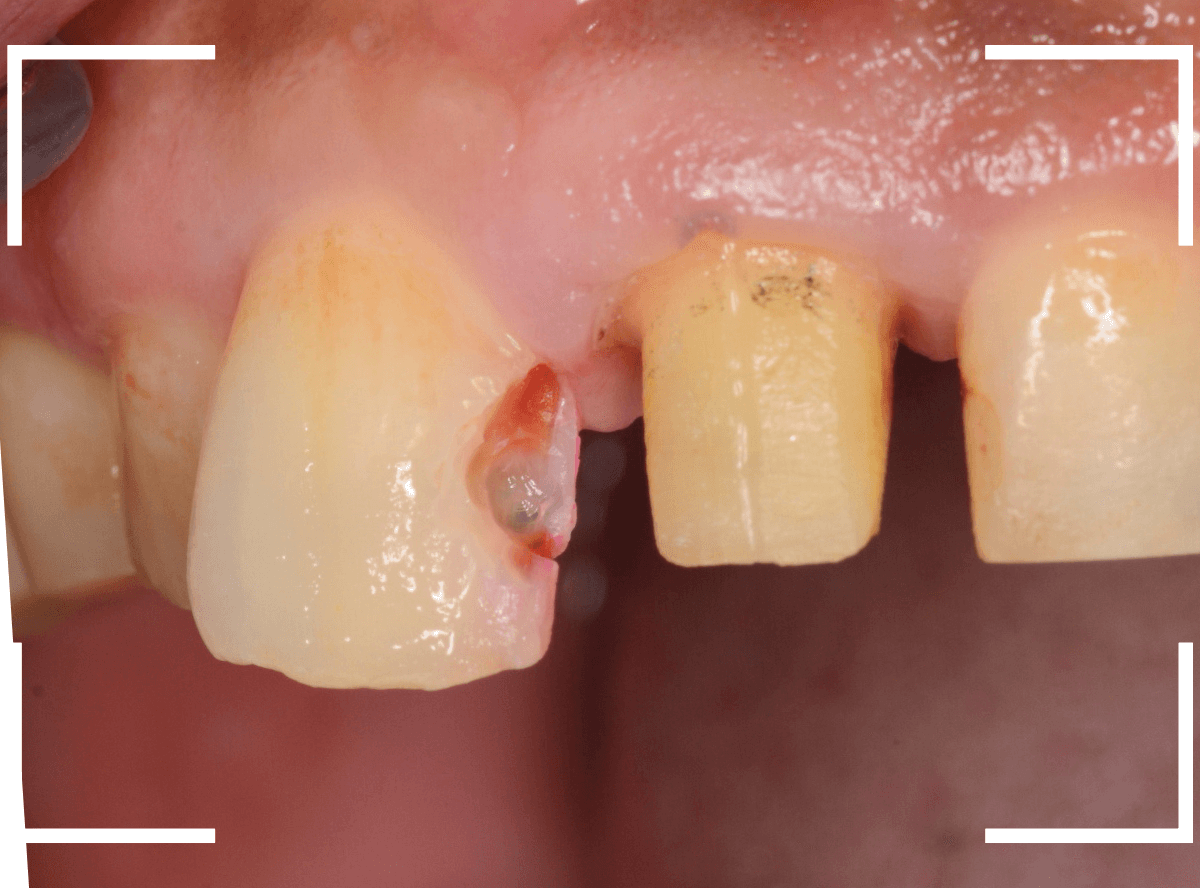

歯を裏側から見たところです。

幸い、見える部分に虫歯が

さし歯と歯肉の間に虫歯ができているのがわかります。

歯の奥まで虫歯が進んでいるのか、浅い虫歯ですんでいるのかは治療をしながら調べていく必要があります。